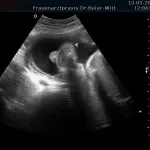

Frühschwangerschaft:

Ultraschall_19